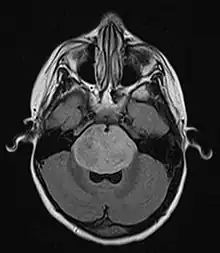

| Brain stem glioma. MRI axial, with contrast | |

Neuroimaging, such as MRI, is the main diagnostic tool for brain stem gliomas. In very rare cases, surgery and biopsy are performed.